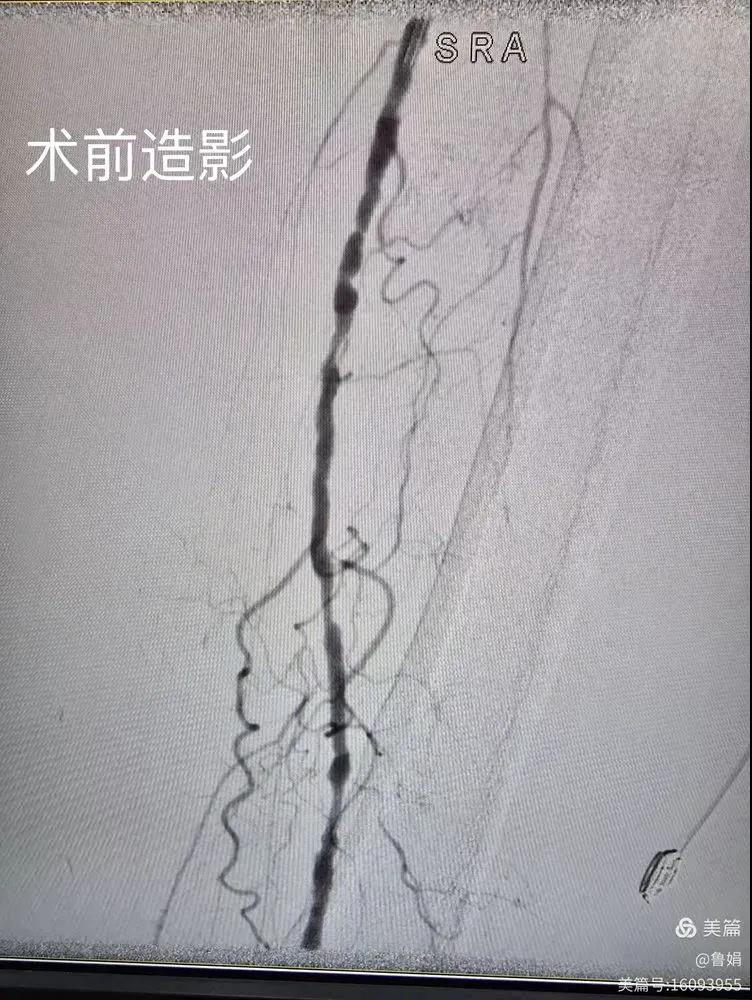

據(jù)悉,該患者,女,73歲,下肢動脈硬化閉塞癥,“以靜息痛,間歇性跛行”入院,CTA評估:股淺動脈,腘動脈間斷性多段重度狹窄,外二科血管外科團隊根據(jù)患者病情,結(jié)合檢查結(jié)果,經(jīng)過科室會診后,決定對該病人行介入治療。手術(shù)由周創(chuàng)業(yè)副主任與北大一院血管外科專家郭宏杰教授聯(lián)合開展,對股淺動脈,腘動脈重度閉塞段行血管開通+藥涂球囊擴張成形,術(shù)后狹窄明顯緩解,血流恢復(fù)!